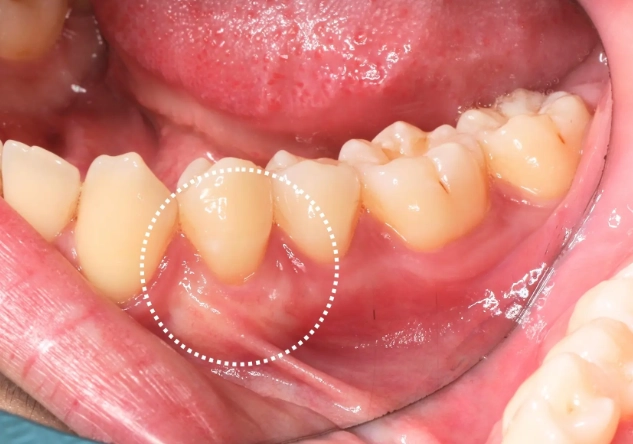

很多人以為牙周手術像剪頭髮,剪掉多少,長回來就應該是多少。但人體組織不是這樣運作的。手術前,你的牙齦處於「發炎腫脹」狀態。想像一下腳踝扭傷腫起來的樣子,消腫後腳踝會恢復原本的尺寸。牙齦也是一樣。

翻瓣手術的核心目的是徹底清除藏在牙齦深處、牙根表面的牙結石和發炎組織。當這些致病原被清乾淨,原先因發炎而充血、腫脹的牙齦組織就會逐漸消腫,變得結實、緊貼牙根。這個「消腫」的過程,在外觀上看起來,就是牙齦高度降低、牙根部分暴露。這其實是組織恢復健康的正面跡象,代表隱藏的感染被控制了。